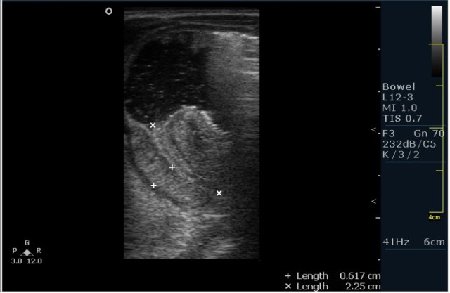

Ребёнок 1 месяц 10 дней от родy, с отсуствием прибавки в весе.

Hypertrophic pyloric stenosis.

Criteria:

1.Pyloric channel > 12 mm in length

2.Muscular layer thickness > 3-4 mm

3.Donuts sign at transverse scanning